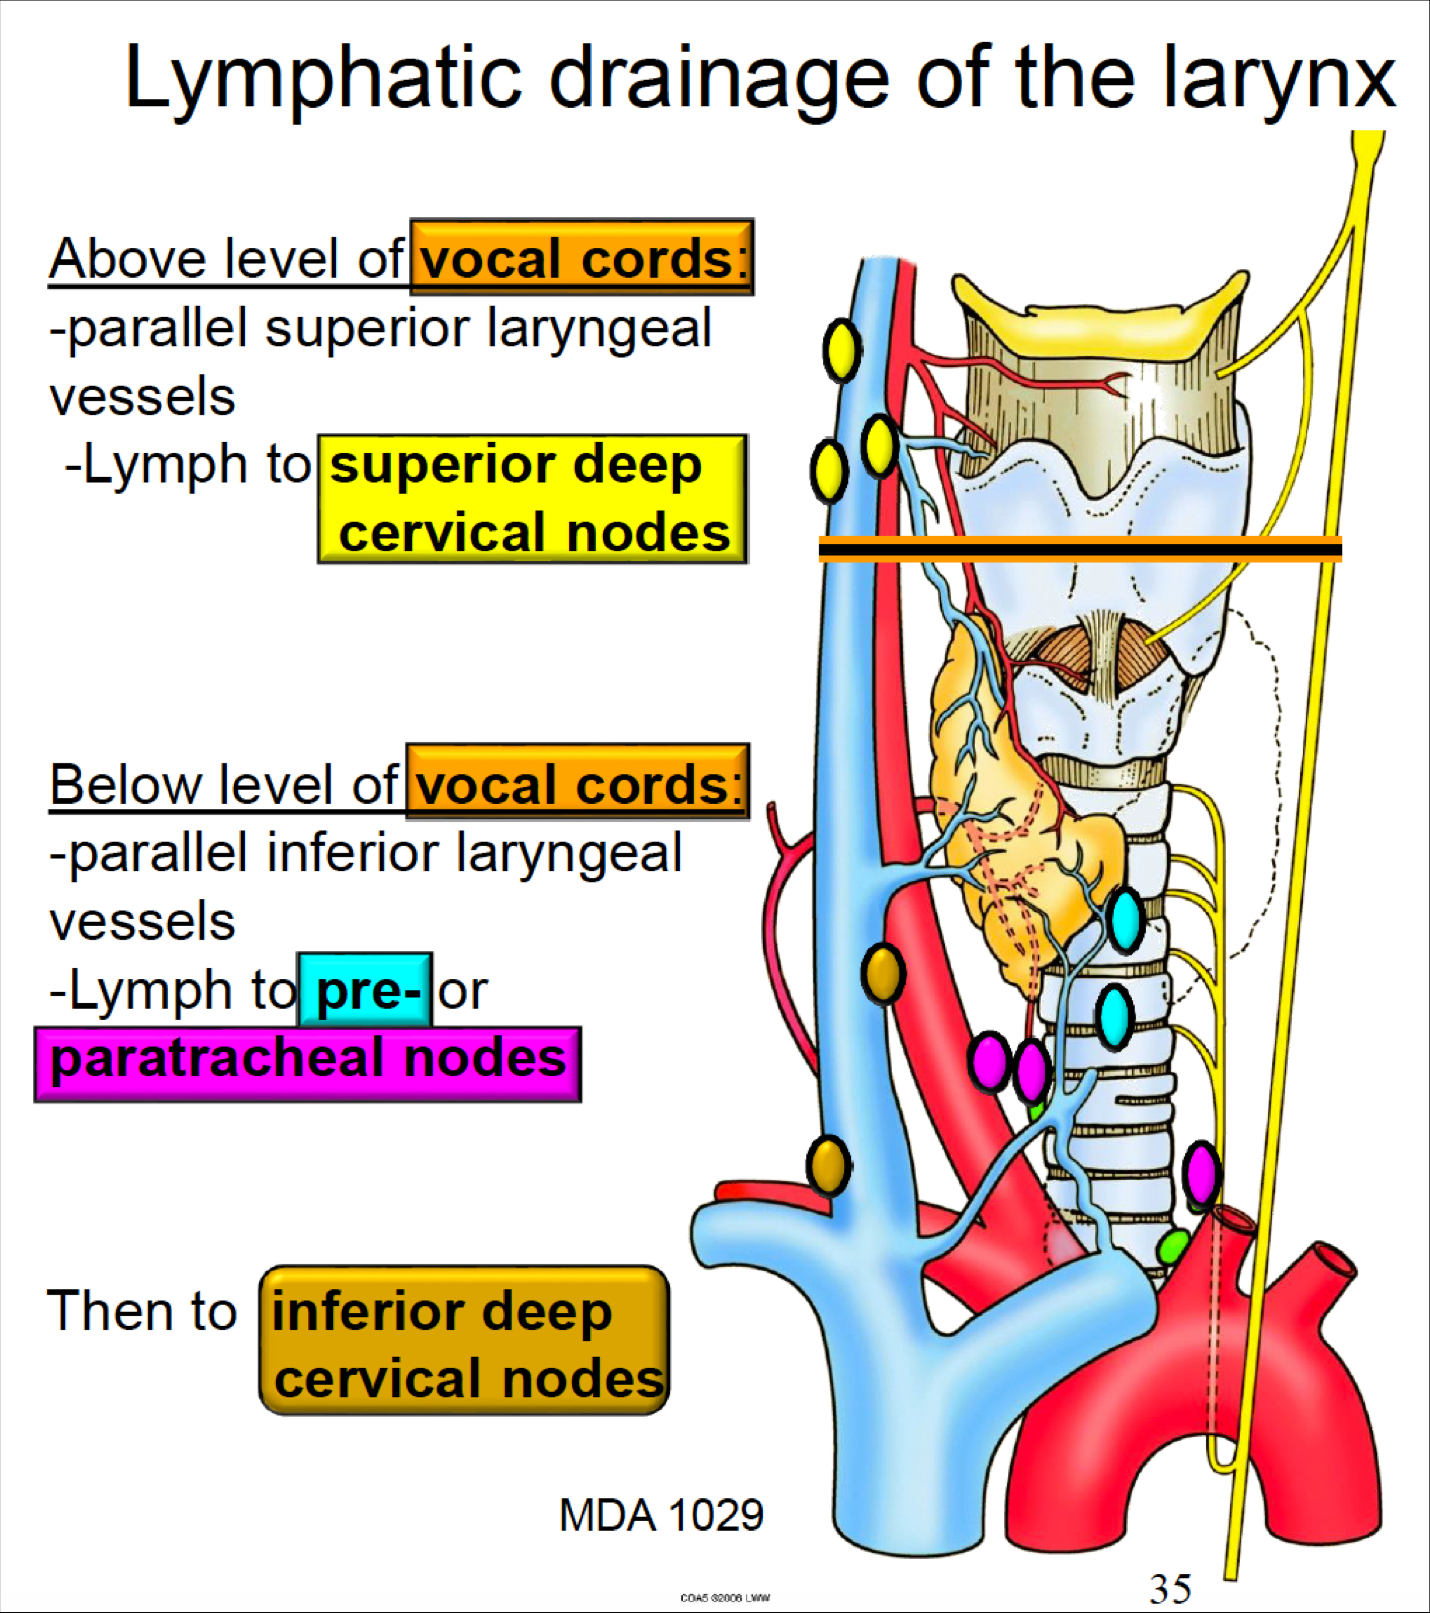

Larynx

用vocal fold 分,上,下分別到SDC, IDC

Larynx

Artery

Nerve

- Sup. laryngeal n.

- Internal br.(Internal laryngeal n.)

- Sensor

- 穿過 Thyrohyoid ligament

- External br.

- Motor

- Internal br.(Internal laryngeal n.)

- Recurrent laryngeal n.

- Inf. laryngeal a.伴行

- 過Cricothyroid joint改叫Inf. laryngeal n.